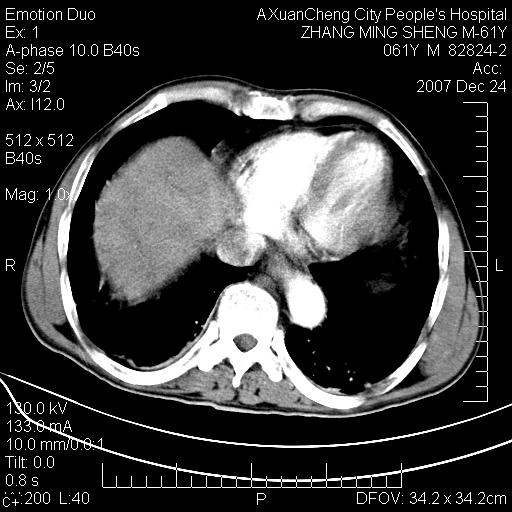

标题: CT11031:M61Y,胰腺占位 [打印本页]

标题: CT11031:M61Y,胰腺占位

大家侃侃门静脉和胆管系统怎么回事,肝内转移?

胰腺癌肝转移

肝硬化,门脉高压,脾肿大;弥漫性肝癌,肝内、门脉、腹膜后淋巴结转移,肝内外胆管扩张,胰头区占位,建议mr检查

胰腺癌伴肝内转移;门脉、肠系膜上v癌栓形成。

考虑为:胰腺癌伴肝脏转移、腹膜后淋巴结转移,门静脉及肠系膜上静脉瘤栓形成。

胰体尾癌伴肝内转移,门静脉及肠系膜上静脉瘤栓形成.